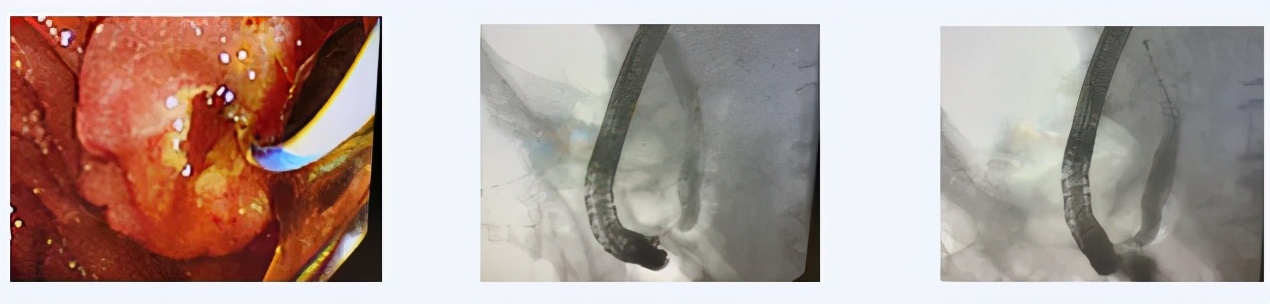

患者90岁,退役老红军,因“心力衰竭,休克状态”收入西青医院心内科,入院后进一步评估病情,确诊为“胆总管结石,急性胆管炎,感染性休克,心力衰竭”,普通外科主治医师王利军会诊后建议转外科病区治疗。该患者转入外科后,完善检查积极抗感染抗休克治疗评估患者病情,考虑患者相关症状均与胆系结石梗阻所致的感染密切相关,考虑到患者高龄,心衰IV级,休克状态,无法耐受手术,且患者危急重症,无法进行全麻治疗,经沟通建议首选局麻下ERCP微创治疗。随后在天津市南开医院内镜专家的指导下,与内镜室护理团队在介入室局麻下,通过十二指肠镜成功为该患者清除胆总管内多发结石放置BD管引流胆汁,解除梗阻后患者病情迅速稳定,恢复良并好出院。